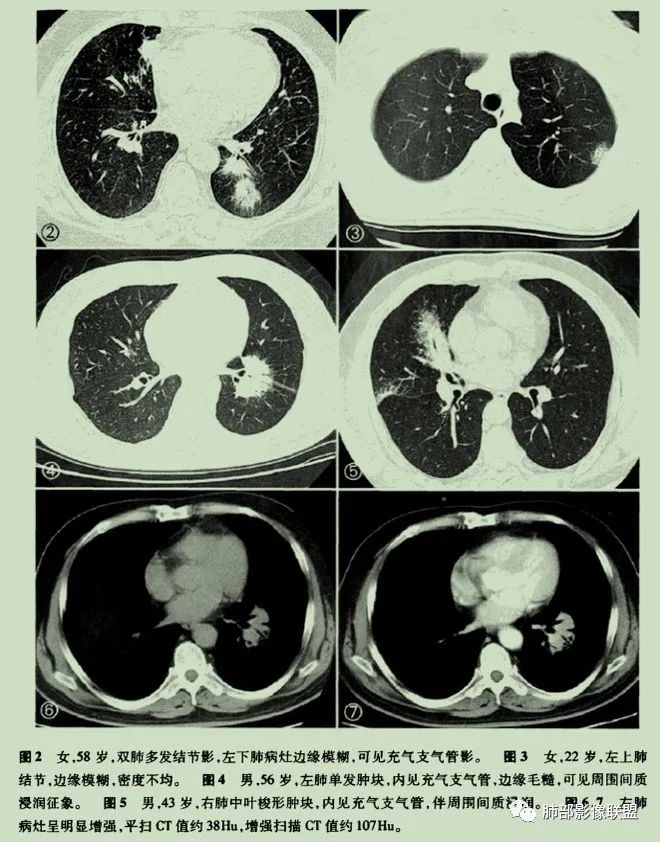

原发性肺淋巴瘤是一种影响肺部的单克隆淋巴样增生,患者在最初诊断后至少 3个月内没有可检测到的胸外淋巴瘤。原发性肺淋巴瘤很少见,占所有原发性肺肿瘤的 0.5%。原发性肺部受累的淋巴组织增生性疾病包括黏膜相关淋巴组织起源的结外边缘区淋巴瘤(MALT)、弥漫性大 B 细胞淋巴瘤(DLBCL)和淋巴瘤样肉芽肿(LYG)。MALT淋巴瘤是一种低级别B淋巴细胞淋巴瘤,由具有局灶性浆细胞样特征的单调小淋巴细胞组成。它们由沿远端支气管和细支气管分布的上皮下淋巴滤泡组成。肿瘤可能有许多关联,其中包括:干燥综合征、异常丙种球蛋白血症、淀粉样蛋白沉积、胶原血管病、幽门螺杆菌感染和艾滋病等。其影像学表现复杂多变,通常表现为孤立的、界限清楚的软组织肿块。不太常见的成像特征包括:多个单侧或双侧结节沿支气管血管束和小叶间隔弥漫性浸润、广泛的肺叶浸润、模拟实变(肺炎)、伴有空气支气管征或磨玻璃样改变。这些由外淋巴结节、间隔和支气管血管周围增厚组成的间质模式看起来与癌性淋巴管炎或结节病所见的相同。

中央淋巴道分布(支气管血管束分布)外周淋巴道分布(小叶间隔和胸膜下分布)

肺淋巴瘤表现多种多样。可表现为多发小结节!

有时表现为渗出性病变、肿块!

或实变+结节!

抗感染无好转的空气支气管征要警惕肺淋巴瘤。

或表现为网格状阴影,少数不典型的患者表现为弥漫性磨玻璃阴影。

有时候诊断不容易,可酷似肺炎!

或酷似肺癌!